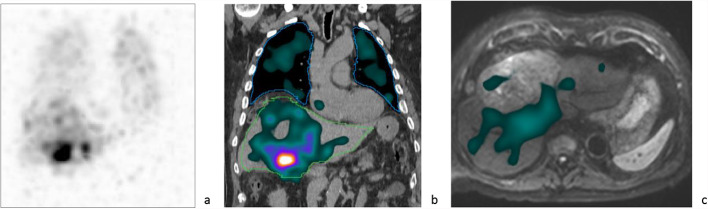

Aim: Prediction of posttreatment lung mean dose (LMD) during liver radioembolization (RE) work-up is essential for risk evaluation of radiation pneumonitis, especially when treating large hepatocellular carcinoma (HCC) where the chance of arteriovenous shunting is not negligible. In case of holmium-166-([166Ho])-RE, either [99mTc]TcMAA or 166Ho-microspheres can be used as scout tracers. Safety of use of 166Ho-scout has been demonstrated previously, but, to our notice, evaluation of lung radiation dose due to 166Ho-scout activity in case of significant lung shunting has not been described so far. Therefore, a retrospective study was conducted to evaluate the presence of pulmonary shunting in HCC patients influencing therapeutical approach and to assess lung 166Ho-scout dose in these patients.

Materials and methods: Twenty-nine HCC patients referred for RE were retrospectively evaluated. All work-ups were performed with 166Ho-microspheres. Scout imaging consisted of a hybrid SPECT/CT acquisition covering the thoraco-abdominal region. As mentioned in the manufacturer's instruction for use of 166Ho-microspheres, the possibility of > 30 Gy lung radiation exposure in a single treatment is withheld as contra-indication for RE. In patients with lung shunt resulting in predicted posttreatment LMD > 30 Gy, lung 166Ho-scout dose due to patient-specific injected activity was calculated, alongside two hypothetical scenarios: lung 166Ho-scout dose related to patient's lung shunt fraction (LSF) assuming administration of leaflet prescribed maximum 166Ho-scout activity and in case of 100% LSF according to patient-specific injected scout activity. Afterwards, these patients were followed for 3 months or till death.

Results: In the 29 patients, average predicted posttreatment LMD was 10.0 Gy (range 0.1-138.9 Gy), four of them revealing predicted LMD > 30 Gy. Based on patient-specific injected 166Ho-scout activity (range 100-200 MBq), average lung 166Ho-scout dose of 0.5 Gy (range 0.1-0.8 Gy) was calculated in these 4 patients. Assuming administration of leaflet prescribed maximum activity of 250 MBq, average lung 166Ho-scout dose would be 0.9 Gy (range 0.4-1.7 Gy). In case of a 100% LSF, average lung 166Ho-scout dose would be 2.2 Gy (range 1.5-2.7 Gy) due to patient-specific scout activity. In these 4 patients, RE was denied and alternative treatment was started. No pulmonary adverse events related to 166Ho-scout were recorded.

Conclusion: This study supports previous reports that 166Ho-scout is a safe alternative to [99mTc]TcMAA -scout and underlines the importance of predicting posttreatment LMD when treating large HCC since 13.8% of our patient group presented arteriovenous shunting with impact on treatment planning.